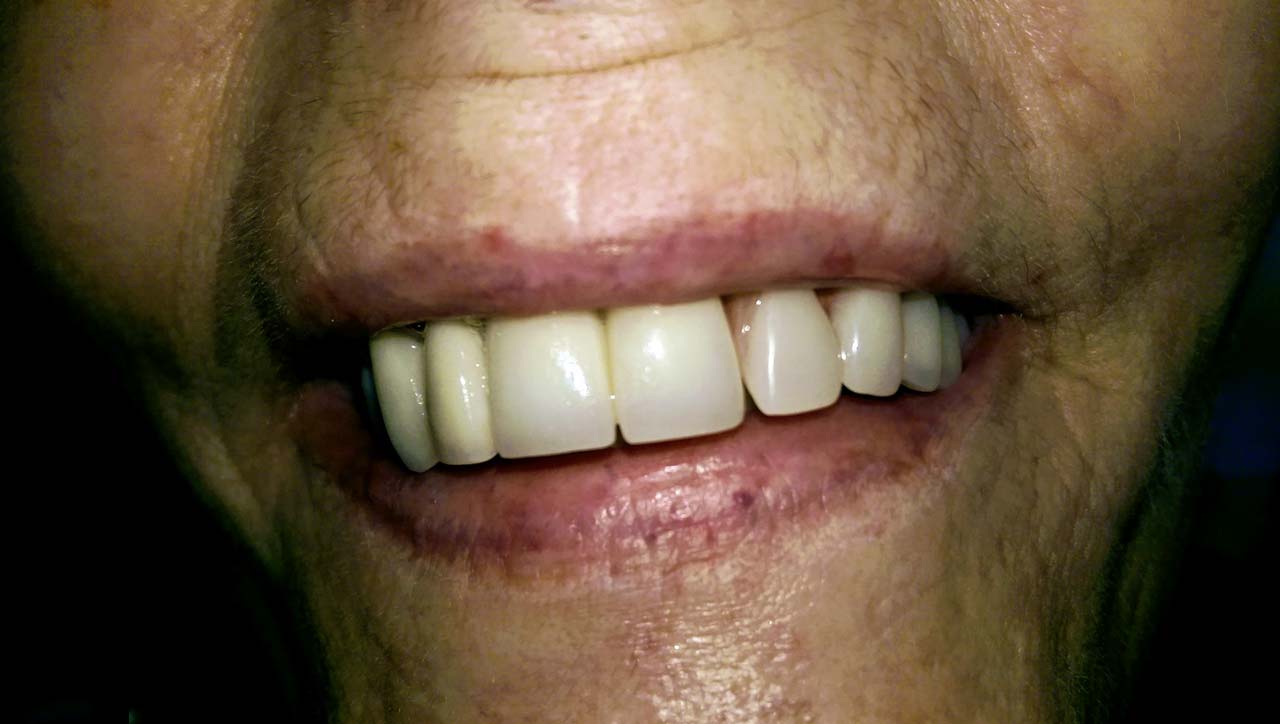

Elhanyagolt fogsor cseréje 2 nap alatt

2 nap alatt varázsoltuk ezt a szép esztétikus alsó, felső körhídat implantátumokkal megtámasztva a korábban elhanyagolt szájba. Az 1. nap 26 fogat távolítottunk el, mert annyira rossz állapotban voltak, és rögtön azonnal terhelhető IHDE svájci implantátumokat raktunk be, fentre 8, lentre 6 darabot. A sebeket összevarrtuk és intraorális szkennerrel digitális lenyomatot vettünk. 2 nap múlva pedig beragasztottuk a kész PMMA műanyag körhidakat. Dr. Kelemen Péter és a Symbion Fogtechnika munkája.